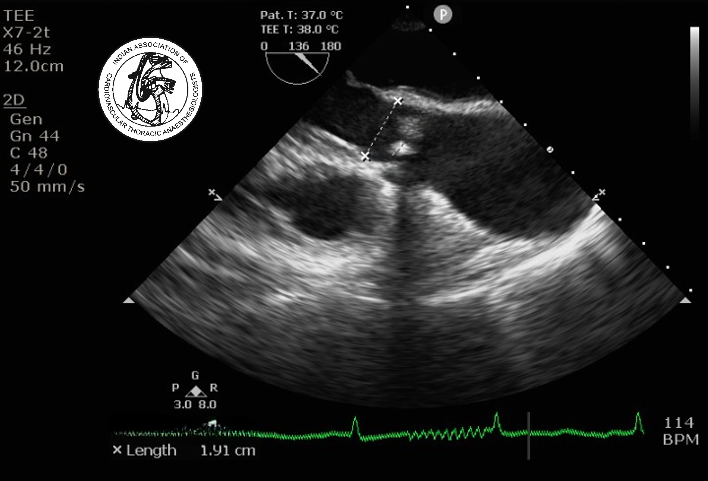

A 60-years-old asymptomatic patient (body surface area 1.5 m2) is diagnosed with severe aortic stenosis. During intraoperative transesophageal echocardiographic examination, the following data are obtained: LVOT peak velocity = 0.6m/s; LVOT velocity time integral (VTI) = 14 cm; LVOT diameter = 1.9 cm; peak velocity across aortic valve = 3m /s; aortic valve VTI = 74 cm, LV ejection fraction of 45%. The patient has a heart rate of 55/min during the study. All of the following statements are correct except:

LVOT cross sectional area == pr2 = 3.14 X (1.9/2)2 = 2.84 cm2

3.Aortic valve area (Continuity equation)

Aortic valve area= LVOT cross sectional area x LVOT VTI / aortic valve VTI

= 2.84 X 14 / 74

=0.54 cm2

It is consistent with Low-flow, low-gradient severe aortic stenosis,  as the ejection fraction is 45%.

Correct Answer: d)It is a classic example of moderate aortic stenosis.